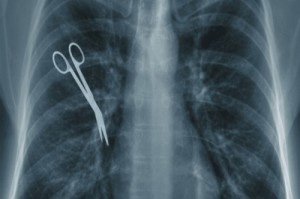

Medical malpractice, also known as medical negligence, can occur in several ways. In some cases, it is the failure to diagnose an illness. In others, it is the improper treatment of one’s illness, whether that be through prescription drug errors and issues or mistakes made during surgery. It can also be delaying treatment for an unnecessarily long amount of time, which can result in the patient’s worsening illness or death. Medical malpractice suits can be leveled against all licensed health professionals, including mental health providers, doctors, and counselors.